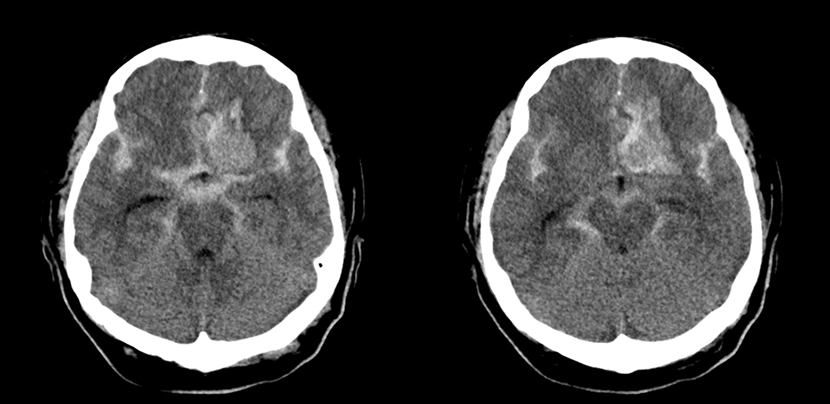

수술전 뇌CT 영상에서 뇌지주막하출혈 소견이 보임

CT 혈관조영술상 뇌동맥류 발견

뇌혈관조영술로 동맥류에 대해 정밀검사

혈관내 코일색전술을 통해 개두술 없이 동맥류를 치료함